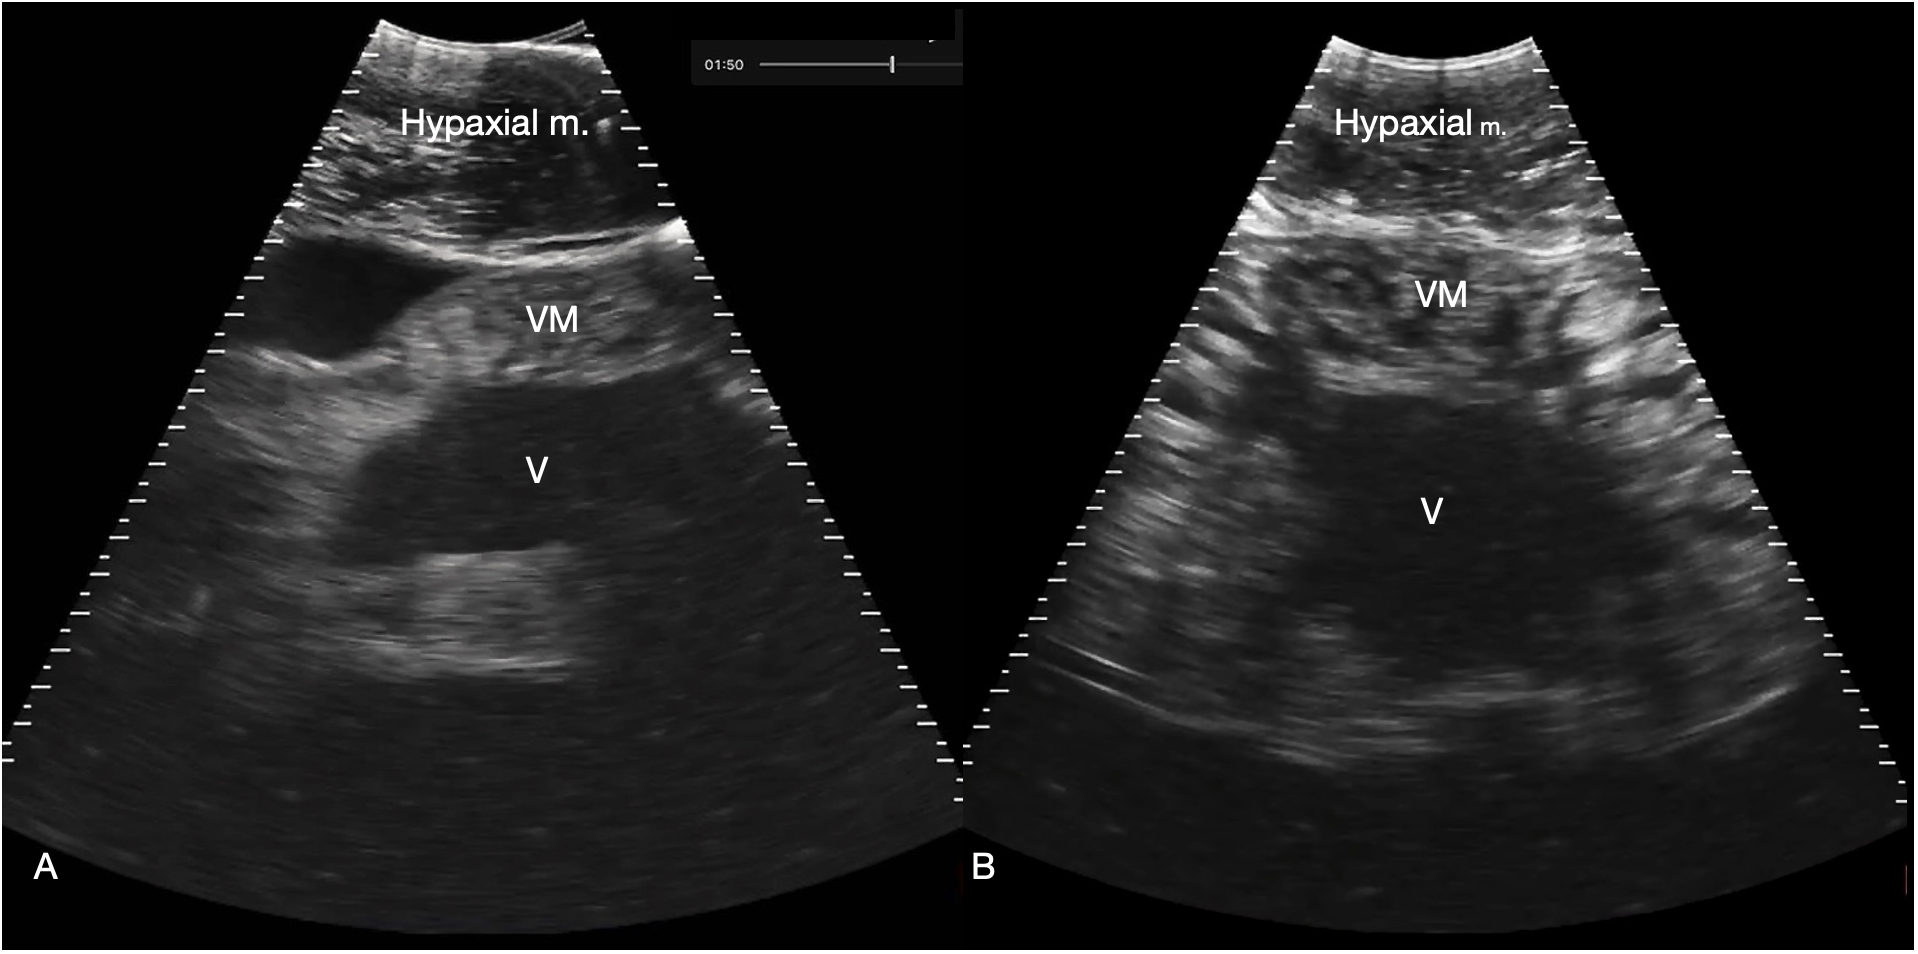

Figure 7

Myocardium. (A) Sagittal ventral sonogram cranial to the pectoral line showing the conus arteriosus, shark 31 (cranial oriented to the left of the image). (B) Sagittal ventral sonogram just cranial to the pectoral line showing the ventricular myocardium, shark 31. Note the striated appearance with alternating hyperechoic (white) and hypochoic (dark) bands within the myocardium. M: Ventricular myocardium, V: Ventricular lumen. See Supplementary Video S6A, B.